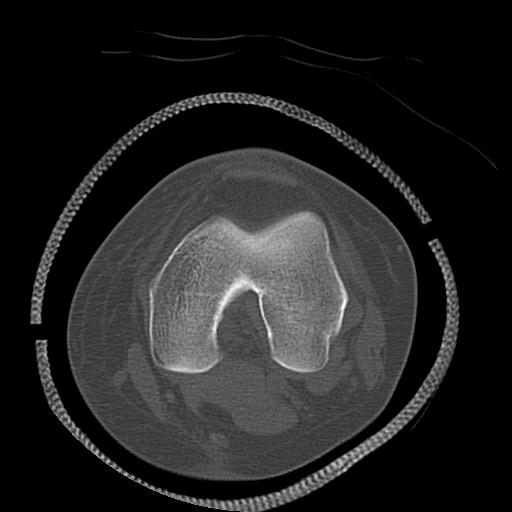

49554 3/13 膝 4R 3/16 4R 1/18 2R 78歳男性 膝蓋骨骨折